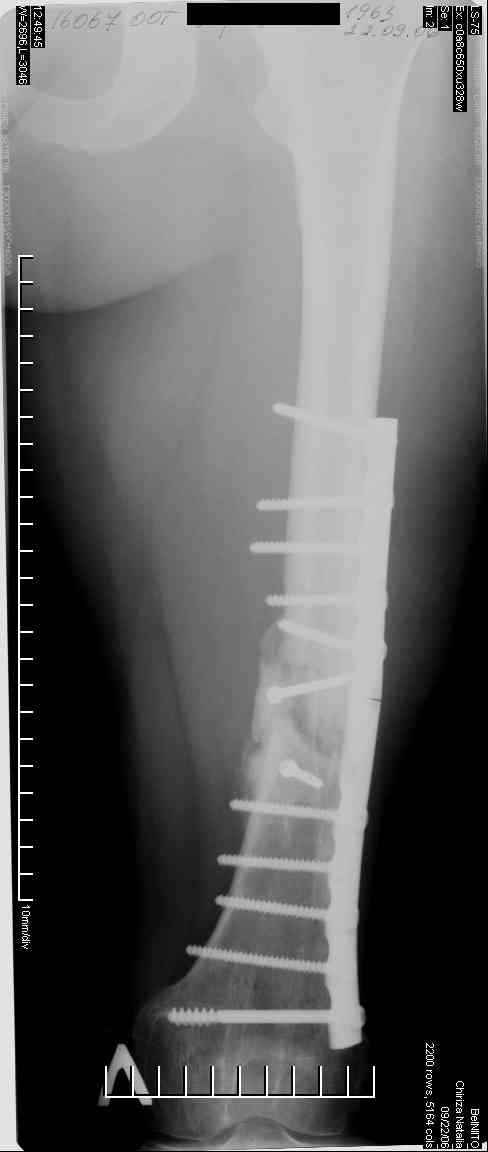

Соматически здорова. В ноябре 2004 года падение с высоты 12 м, перелом правой вертлужной впадины со смещением, неврит седалищного нерва, откр. перелом дистального отдела большеберцовой кости справа и закрытый перелом с/н/3 левого бедра. К нам поступила через 3 недели после травмы, был выполнен в 2 сессии сначала интрамедуллярный ретроградный остеосинтез бедра слева, затем остеосинтез вертлужной впадины и голеностопа справа. При остеосинтезе бедра пришлось немного приоткрыться в зоне перелома для репозиции и вообще операция затянулась часа на 2.5-3 (это один из наших первых интрамедуллярных синтезов). Через 4 месяца при нагрузке весом около 50 кг постепенно развилась варусная деформация бедра с искривлением стержня. Закрыто выпрямили под наркозом, динамизация гвоздя,но в сентябре 2005 г. согнулось бедро снова. Гвоздь удалили, остеосинтез пластиной, декортикация, пластика спонгиозой из метафиза б/берцовой кости. Динамика заживления вялая, но конструкция стояла неплохо (без признаков расшатывания), постепенно дали нагрузку - в марте 2006 года - перелом пластины - реостеосинтез пластиной, пластика гребнем подвздошной кости. На контролях (за август, т.е. 4 мес. после операции - прилагаю) динамика положительная, разрешена нагрузка до 50 кг. В начале этой недели без падения вновь появились боли в бедре - на Р-граммах - перелом пластины (снимки прилагаю).

Фоном ко всему этому то, что и перелом вертлужки и дистального отдела б/б кости тоже не срастаются, хотя на голени уже дважды выполнялась костная пластика, на впадине - вторичное смещение, перелом части металлоконструкций. Исследовали гормональный фон - парат-гормон и прочие щитовидные в норме, месячные регулярно.